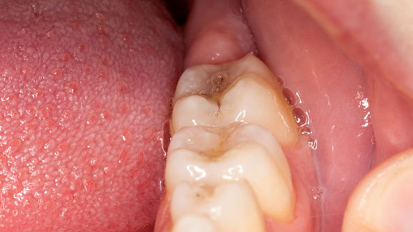

Raziskovalci so odkrili morebitne biomarkerje za zobno gnilobo

Odense, Danska / VALENCIA, Španija: Za določitev potencialnih biomarkerjev za zobno gnilobo, je mednarodna skupina raziskovalcev podrobneje raziskala ...